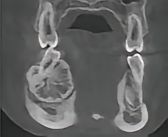

非均质性成牙骨质细胞瘤